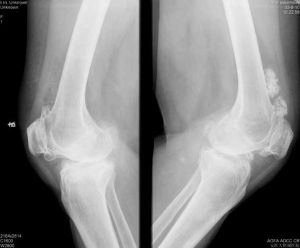

診斷骨癌x射線:根據x線片表現,骨肉瘤病變周圍梁膜或骨密度增加,並引起骨膜反應性成骨。

體格檢查、實驗室檢查以及X線攝片可獲得有價值的診斷根據,如病史中的發病年齡對診斷有一定的參考價值。體檢及X線表現中的發病部位對診斷亦有參考意義。

4、x線所見;良性骨腫瘤的界限多比較清楚,與正常骨質之間常有明確的分界線,一般無骨膜反應,如有反應,骨膜新骨也比較規則、整齊。惡性骨瘤則邊界不清楚,與正常骨質之間分界不清,骨膜反應紊亂,甚至形成日光放射狀。